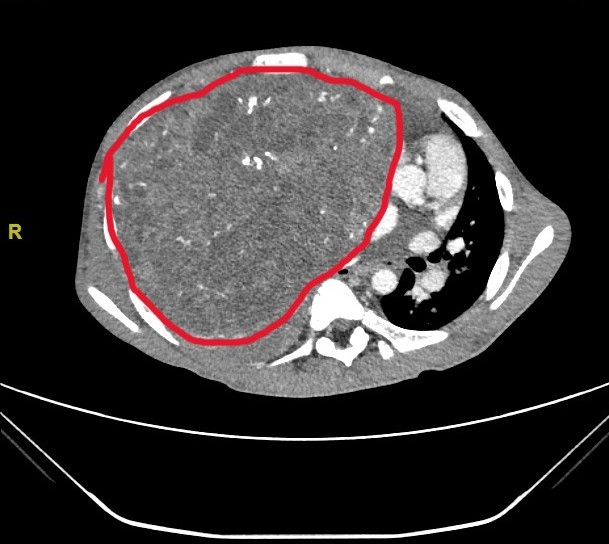

小宇体内的纵膈肿瘤尺寸达29×27×15厘米,长满右侧胸腔并延伸到左侧,将心脏从正常位置挤压到左侧胸壁边缘,并严重压迫周边脏器、影响心肺功能。更棘手的是,肿瘤血供丰富,与周围组织粘在一起,手术切除风险极高,极易引发致命性大出血。

3月13日,麻醉科副主任医师郭东东及团队全程严密护航,丁建勇和儿科医院心胸外科副主任医师张文波密切配合,精细操作,逐层剥离,最终成功将肿瘤完整切除,术中出血不到100ml。切下的肿瘤重达7斤3两,超过了成年人头颅大小。术后小宇心肺压迫即刻解除,顺利转入康复治疗,本周即可出院。